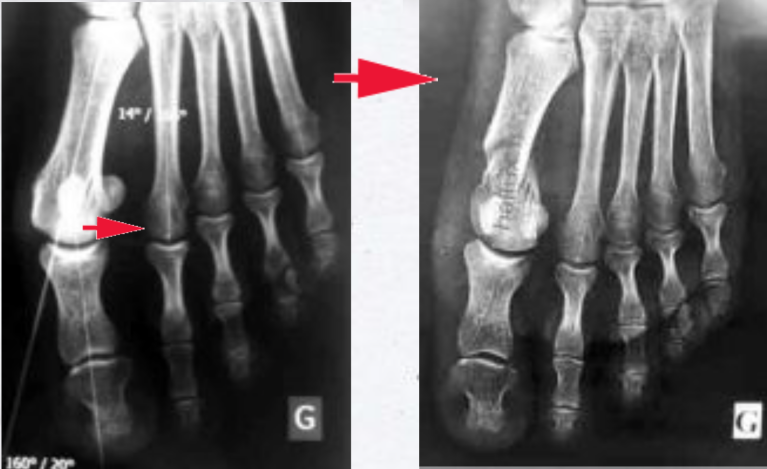

RADIOGRAPHIES

(biseau par voie mini-invasive)

Ces radiographies montrent la correction de l'hallux valgus ; la translation de la tête du premier métatarsien permet de la rapprocher de la tête du deuxième métatarsien. L'espace entre ces deux métatarsiens est réduit. L'angle inter-métatarsien est normalisé.

La forme et la taille de la tête métatarsienne restent physiologiques. La surface articulaire, contrairement à d'autres techniques où l'on rabote la tête, est intacte, sans réduction de surface. Son orientation peut être corrigée.

Enfin, on peut observer que les sésamoïdes, petits os normalement situés sous la tête du premier métatarsien, ont retrouvé leur position normale, non luxés...

L'intervention de biseau est une opération physiologique, qui s'efforce de restituer une anatomie normale avec des angles inter-métatarsien et métatarso-phalangien normaux, sans altération ni diminution de la surface articulaire.